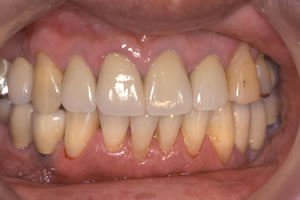

インプラント歯を抜いてしまったりして、元になる歯がない場合に、顎(あご)の骨に人工の歯根を作り、その上に歯を形成します。 歯根になる部分には「チタン」という素材を使いますが、顎(あご)の骨に良くなじむため、自分の歯と同様に使うことが出来ます。 症例1![]() 処置前

![]() 処置後